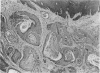

Intra-oral squamous-cell carcinomas occurred in over 50% of the HMT inbred strain of rats. In the outbred stock from which it was derived the incidence was 5% or less, both when inbreeding was begun and after the inbred strain was fully established. Various factors in food and husbandry which might have irritated the oral mucosa were investigated, but there was no signficiant evidence that they played any part in the high incidence of mouth tumours. It is concluded that there must have been an accidental selection during inbreeding in favour of rats which had an inherited tendency to develop squamous-cell carcinoma of the mouth. There are a number of similarities between the rat tumour and intra-oral squamous-cell carcinoma in man and it is suggested that the rat tumour could be used as a model of the human disease.